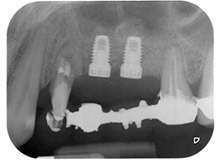

Les implants (Restore, Keystone Dental, 3,75 mm de diamètre, 8,0 mm de long) ont été mis en place à l'aide du moteur d'implantologie (Fig. 11 et 12).

Enfin, après incision du périoste, le site a été suturé avec repositionnement passif d'un lambeau d'avancement coronaire, à l'aide d'un matériau de suture résorbable 5-0 (Fig. 15). La radio postopératoire montre les deux implants dans leur position verticale correcte (Fig. 16).